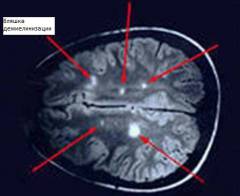

Показатели, выявляемые при КТ и ЯМР:

- утолщение нерва;

- очаг демиелинизации;

- сдавливание нерва.

Электромиография регистрирует активность мышечных волокон с помощью игольчатых или накожных электродов. Ответы мышцы фиксируются в виде биоэлектрического потенциала, который можно регистрировать с помощью осциллографа и отображать на фотоплёнке или экране. При невропатиях наблюдается снижение мышечной силы. На начальных стадиях фиксируются небольшие изменения в активности, но со временем мышцы могут полностью атрофироваться и терять электрический потенциал.

Кроме этих методов, существуют и другие подходы для выявления причин невропатии, такие как компьютерная томография (КТ) и ядерно-магнитный резонанс (ЯМР). Эти исследования помогают выявить структурные изменения в нервах и головном мозге.

- утолщение нерва при воспалительных процессах;

- очаги демиелинизации или бляшки, характерные для рассеянного склероза;

- сдавливание нерва анатомическими структурами (позвонком, суставом) при травматической невропатии.